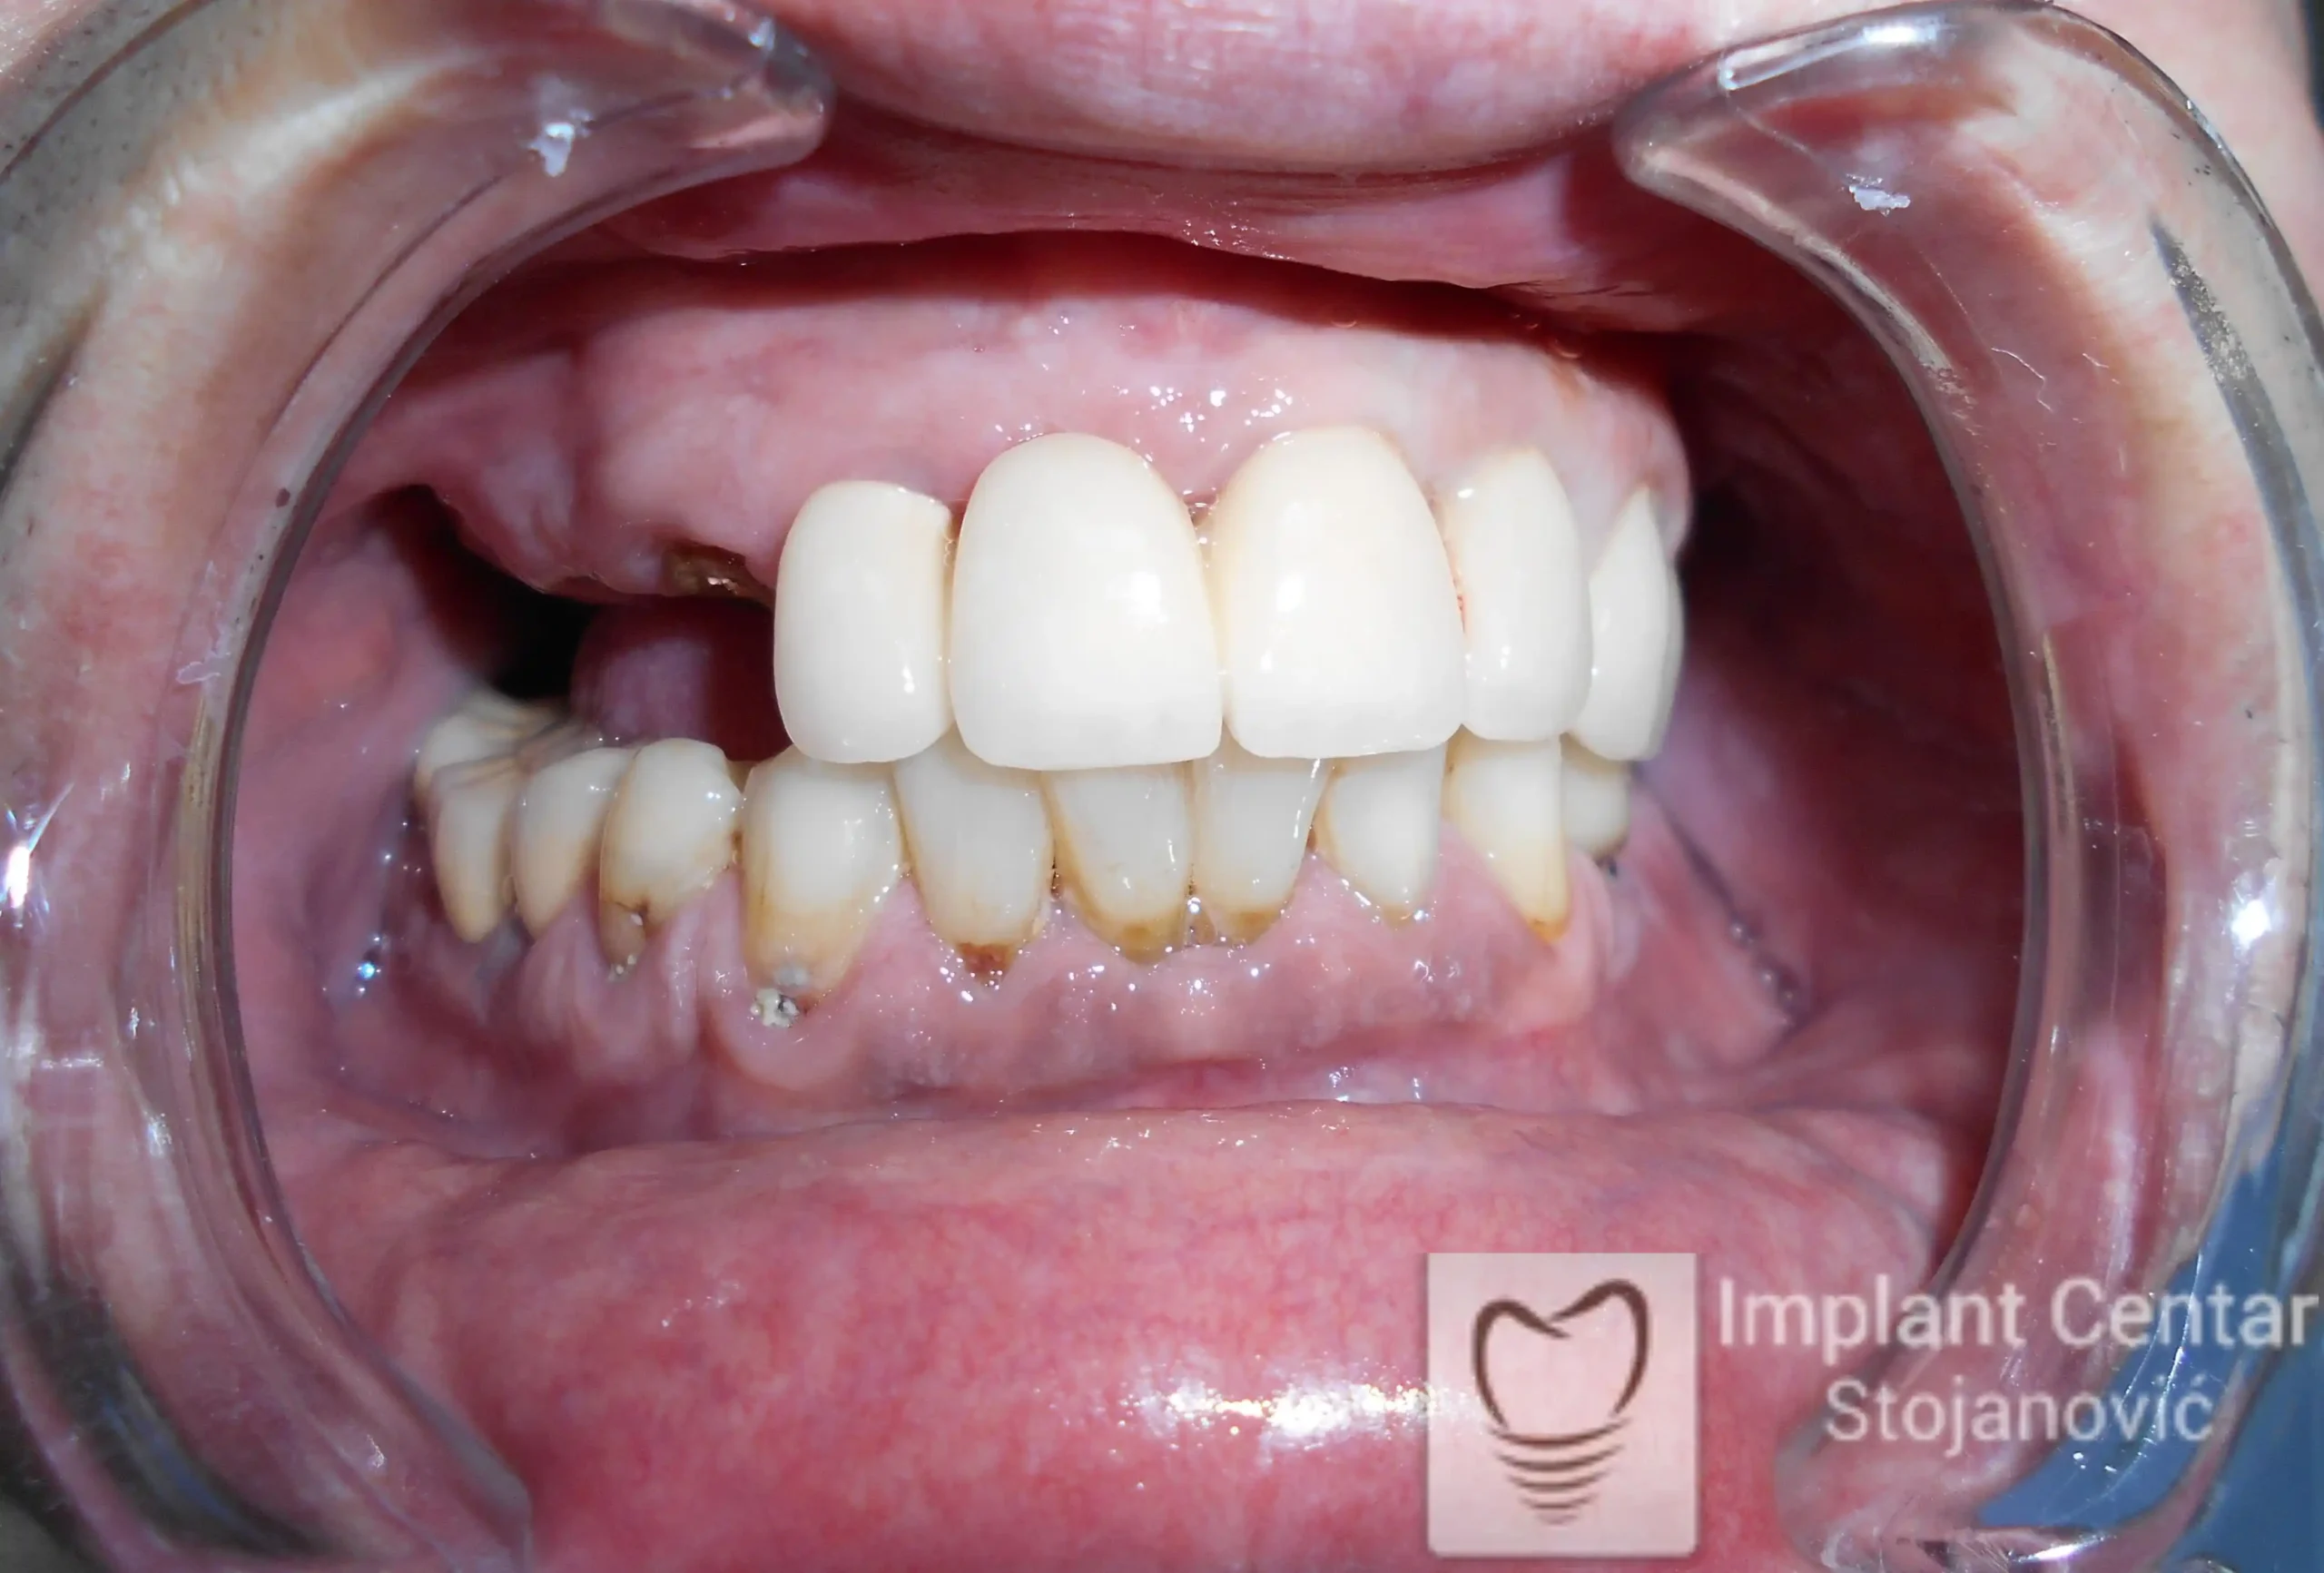

Na slici 1. i slici 2. prikazan je izgled pacijenta pre početka terapije – klinički i rendgenološki.

Nakon vađenja zuba, ugrađeni su implantati. Na slici 3 prikazan je ortopan snimak sa ugrđenim implantatima. Tokom perioda osteointegracije, pacijent je bio zbrinut fiksnim privremenim krunicama na implantatima, koje su izrađene samo dva dana nakon hirurške intervencije.

Na slikama 5. i 6. prikazan je izgled definitivnih cirkonijum-keramičkih mostova na implantatima.

Pacijent je izuzetno zadovoljan — kako estetikom novog osmeha, tako i funkcijom, jer ponovo može bez problema da jede i da se smeje.